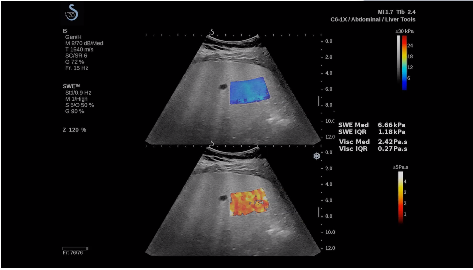

法國(guó)聲科影像(SuperSonic Imagine,SSI. Euroniex:FR0010526814)近日發(fā)表公告,宣布其研發(fā)的新一代“極速”超聲成像平臺(tái)(UltraFast Imaging),首次實(shí)現(xiàn)了肝臟的多項(xiàng)超聲定量評(píng)估新指標(biāo)同步檢測(cè),包括:Att PLUS,SSp PLUS和Vi PLUS等,基本涵蓋肝臟相關(guān)病理變化指征的如纖維化、脂肪變、炎癥等。據(jù)悉,此多項(xiàng)新技術(shù)新將搭載于新Aixplorer系列E超系統(tǒng)。

E超相關(guān)技術(shù)已被多項(xiàng)多中心大樣本研究證實(shí)對(duì)于肝纖維化無(wú)創(chuàng)評(píng)估有重要意義,同時(shí)也可全面應(yīng)用于乳腺、甲狀腺、肝臟、前列腺、肌骨、婦科等全身各組織器官的定量評(píng)估和鑒別診斷。在慢性肝臟方面,聲科E超的肝臟相關(guān)定量診斷技術(shù)集,于2018年獲得美國(guó)FDA認(rèn)證,成為FDA歷史上首次獲批的單病種超聲全面定量解決方案。